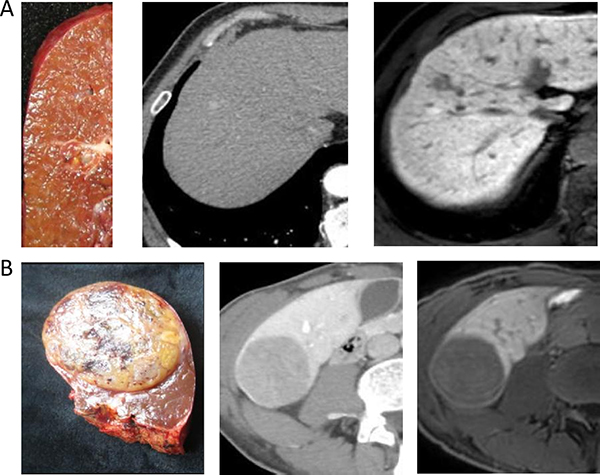

Based on pathological macroscopic examination of the 94 HCCs, six tumors (6.4%) were classified as SN-IM (Figure 1A), 32 (34%) as SN-DM (Figure 1B), 26 (27.7%) as SN-EG (Figure 2A), 21 (22.3%) as CMN (Figure 2B), and nine (9.6%) as IF (Figure 2C). Therefore, 38 nodules (40.4%) were classified as SN and 56 (59.6%) as non-SN. Fifty-one (54.3%) tumors were ≤ 3 cm in size and 43 (45.7%) were > 3 cm. Mean sizes of all tumors, only SN types, and only non-SN types, were 3.7 ± 2.2 cm, 2.9 ± 1.8 cm, and 4.2 ± 2.3 cm, respectively.

Figure 1: (A) A 66-year-old man with cirrhosis related to hepatitis B. The gross classification was SN-IM based on pathological examination. Two images following specimen were arterial phase of CE-CT and hepatobiliary phase of EOB-MRI. (B) A 62-year-old man with cirrhosis related to hepatitis B. The gross classification was SN-DM based on pathological examination. Two images following specimen were equilibrium phase of CE-CT and hepatobiliary phase of EOB-MRI.